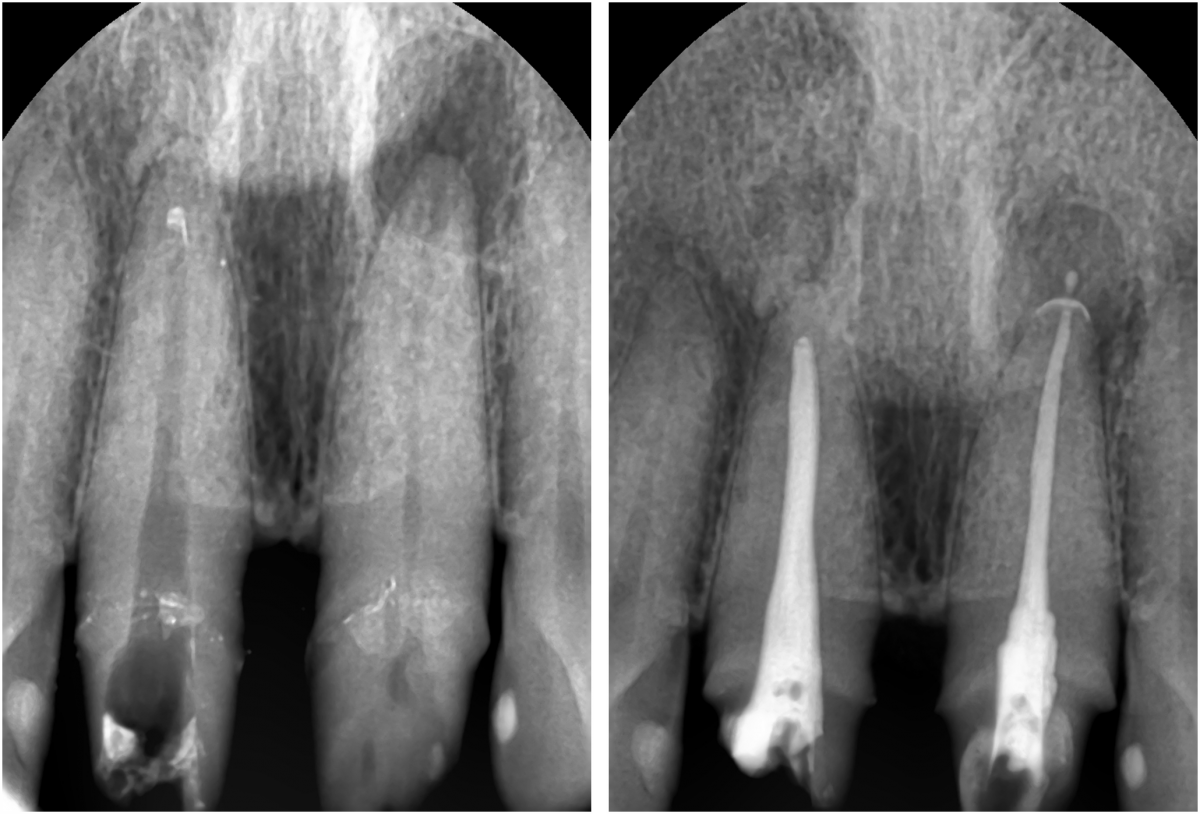

Apicorctomy /central incisor /GBR ; 6-year follow up.

<CJ SBN> Apicorctomy /central incisor /GBR ; 6-year follow up.